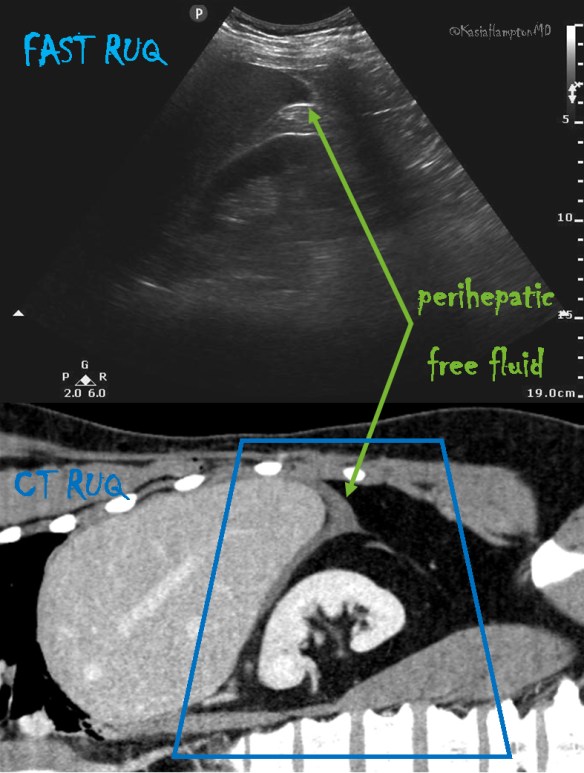

The RUQ FAST scan:

Seek and ye shall find 3

FAST ultrasound evaluation was performed after the patient was log-rolled in both directions – first to the left and then to the right.  Subsequently the patient was taken to CT scan. He remained hemodynamically stable. Below the comparative findings of FAST vs CT scans.

IMAGING

FAST ULTRASOUND

CT

RUQ

perihepatic free fluid

SUBXIPHOID

no pericardial effusion

LUQ

no free fluid

trace perisplenic free fluid

PELVIC

Given stab wound to left anterior chest with presence of free fluid in the abdomen (with hepatic and splenic injuries identified on CT), patient was taken to the operating room. Injury to pericardium itself without pericardial effusion was suspected on CT. During the surgical exploration it appeared that the stab wound to the left chest only nicked the pericardium (no blood within pericardial sac), while penetrating the left diaphragm, left lobe of the liver, stomach, spleen and pancreatic body.